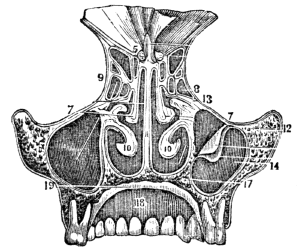

| 43. | Anatomy of the Organs of Smell, | 389 |

| 43. | Physiology of the Organs of Smell, | 391 |